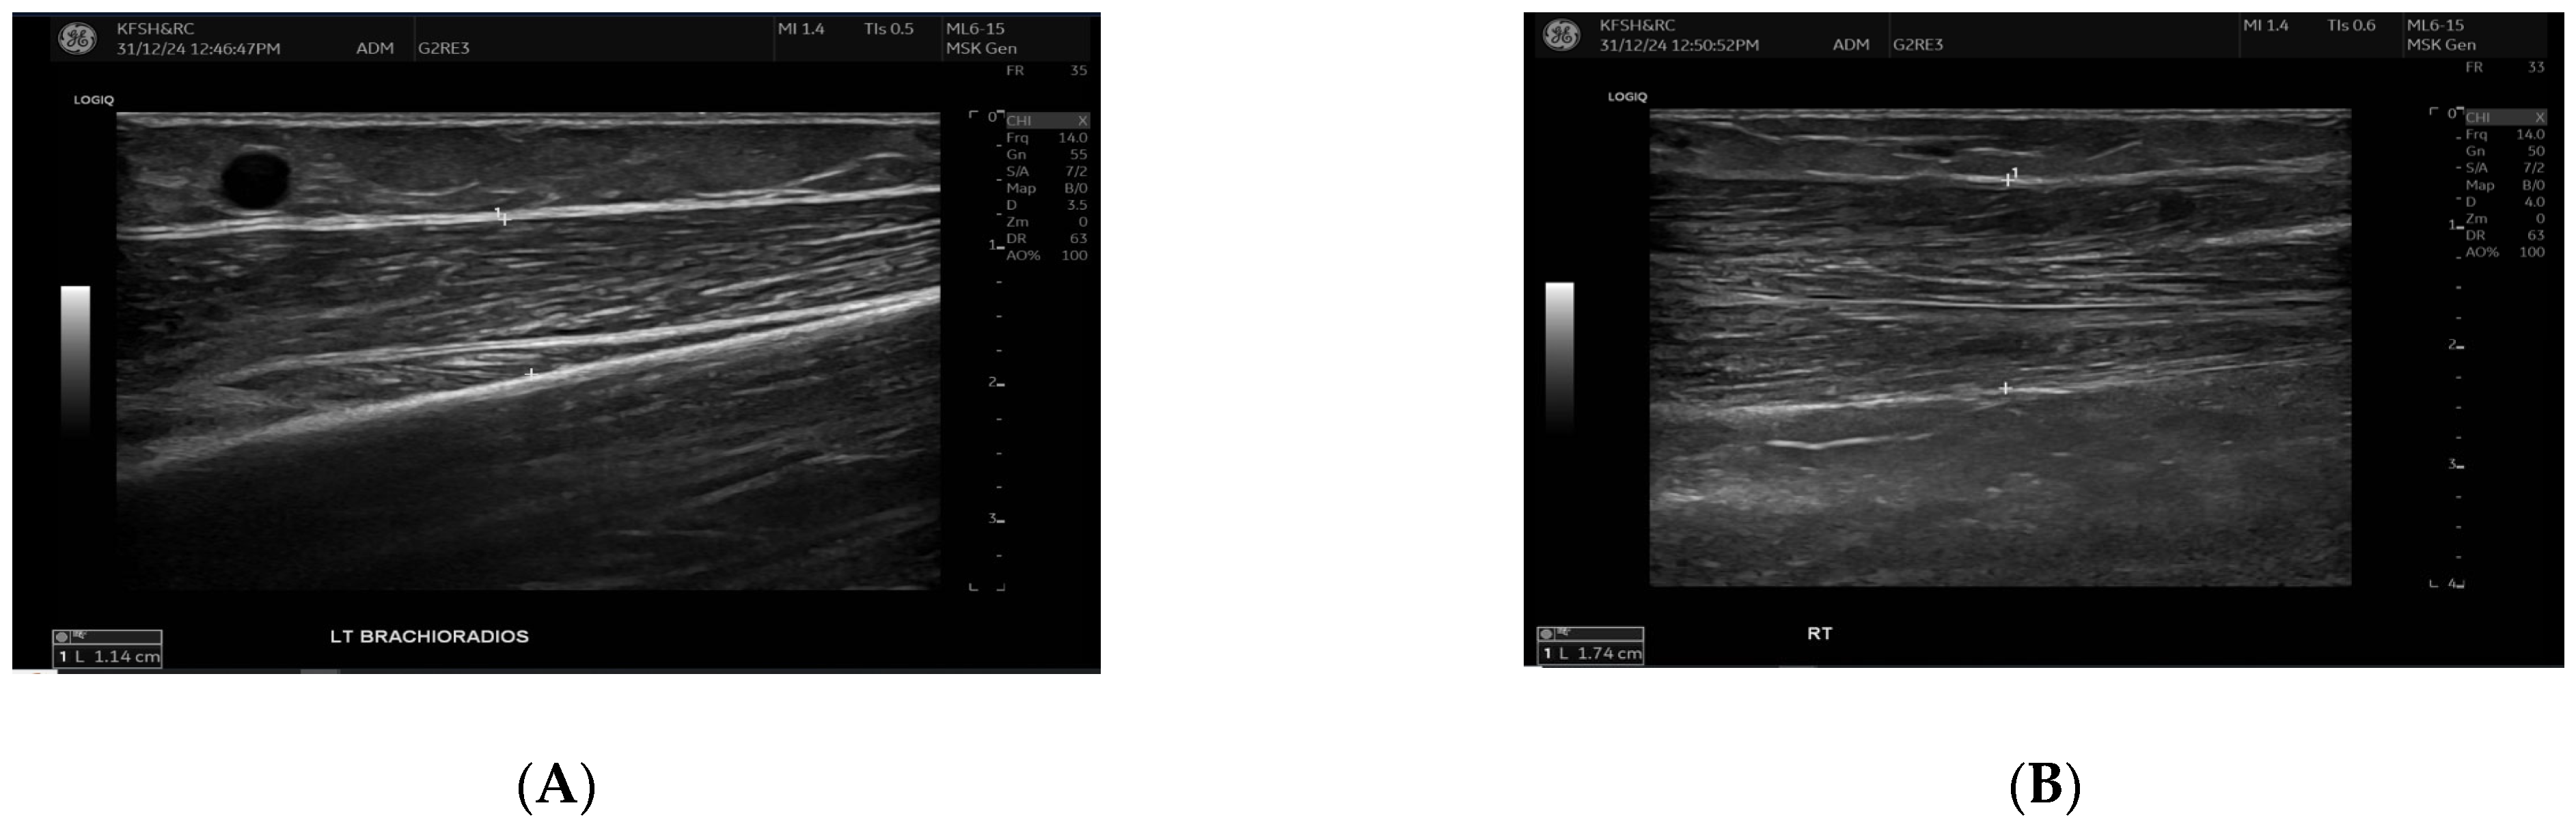

Figure 2.

This figure demonstrates the comparison of brachioradialis muscle thickness between the fistula (A) and the contralateral arm (B). B-mode ultrasound images showing brachioradialis muscle thickness measurements. The left panel (A) (fistula side) demonstrates reduced muscle thickness (1.14 cm) compared with the contralateral arm (right panel (B), 1.74 cm). Measurements were obtained in the mid-muscle belly using a linear high-frequency transducer.